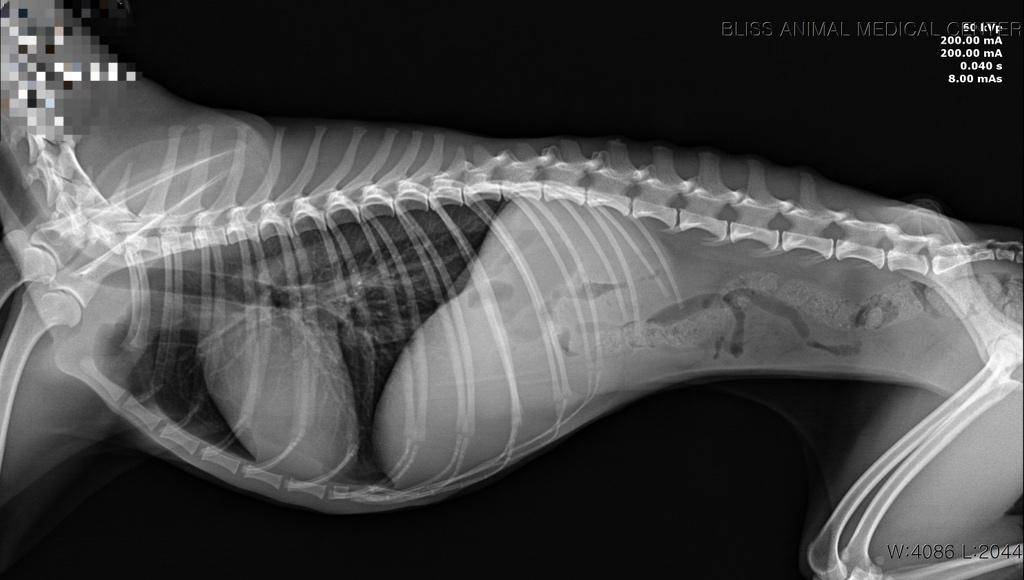

7월 16일에 강아지가 무기력하더니, 17일 새벽에 1번, 병원에서 2번, 내원 후 집에서 1번 총 4번 발작했습니다. 검사해 보니 췌장염도 있고, 심장병(단계 설명은 못 들음), 간 문제 등등 그 외에도 문제가 많이 보여서 수의사 님도 정확히 뭐 때문에 발작을 했는지 확답을 내리지 못 하셨습니다.

이 나이에 이렇게 아픈 것도, 체격/먹는 거에 비해 살이 안 오르는 것도 선천적 요인일 가능성이 높다고 하셨습니다.

이런 상황이라면 뇌 외성 원인을 잠정적으로 배제할 수 있는 수준이라 뇌외성 이상 즉, 두개골 내의 이상을 평가하기 위한 MRI 검사가 추천됩니다.

뇌내 이상은 혈액검사에서 특별한 변화를 보이지 않거나 위 자료처럼 애매하게 나오는게 일반적이기 때문입니다.